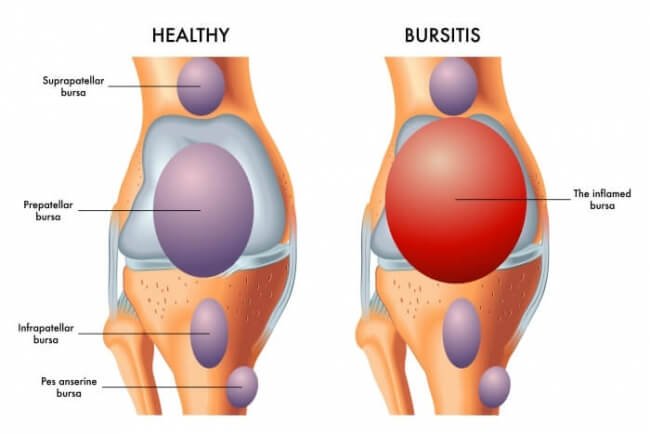

Joint Infection (Septic Arthritis)

Joint infections occur when bacteria infect the joint space, leading to severe pain, swelling, stiffness, and pus formation. Immediate Joint Infection Treatment in Indore is required to protect the joint cartilage and maintain mobility.